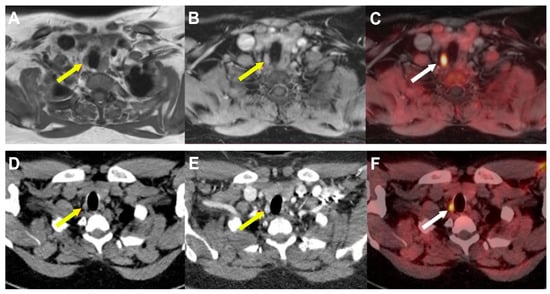

Multiplanar and maximum intensity projection (MIP) images are then evaluated. The classic appearance of an enlarged parathyroid gland on 4D-CT scans is an ovoid soft tissue lesion with the longest diameter greater than 6 mm, hypodense to the thyroid tissue on the non-contrast phase with greater contrast enhancement on the arterial phase and wash-out on the delayed phase (Figure 4).

Figure 4. Enlarged left superior parathyroid in 53-year-old woman with primary hyperparathyroidism. Yellow arrow indicates 9 mm soft tissue nodule located posteriorly to third medium of left thyroid lobe, hypodense to thyroid parenchyma on non-contrast-enhanced phase (A), hyper enhancing on arterial phase (B) with subsequent wash-out on delayed phase (C). Reformatted sagittal (D), coronal (E), and axial (F) maximum intensity projection images obtained by arterial phase scan demonstrate upper enlarged polar vessel.